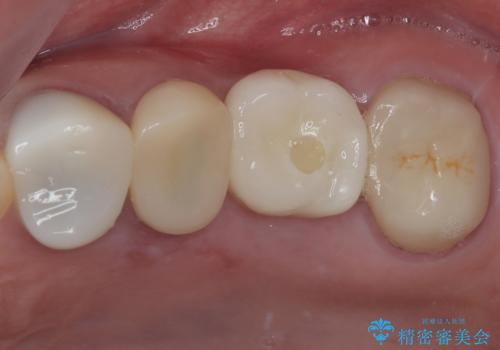

奥歯がしみる オールセラミッククラウンによる奥歯のむし歯治療